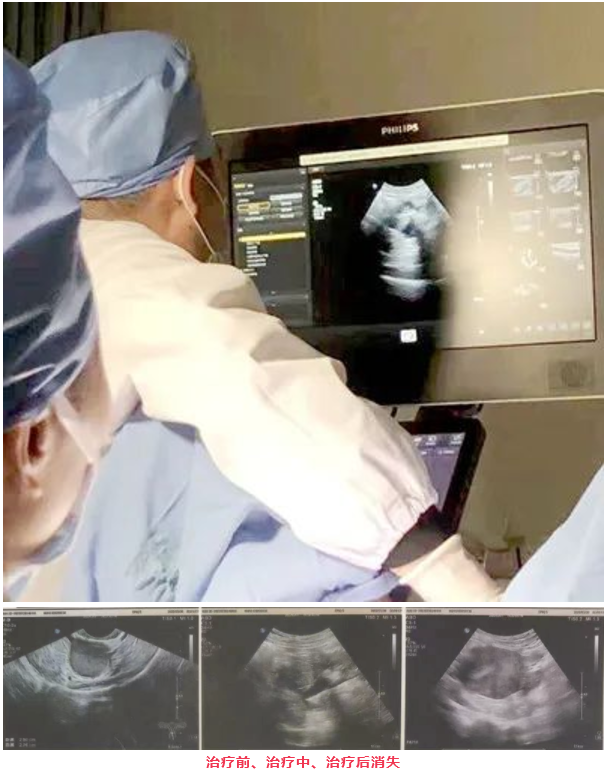

在顾爱玲主任和谈卫杰主任的默契配合下,术中穿刺顺利:抽出咖啡色样粘稠液体25ml,直至囊肿消失,后用生理盐水反复冲洗至抽出清亮液体,术后囊内注药硬化剂治疗,抽出囊液送脱落细胞学检查。

治疗术后复查彩超:囊肿消失,患者安返病房。